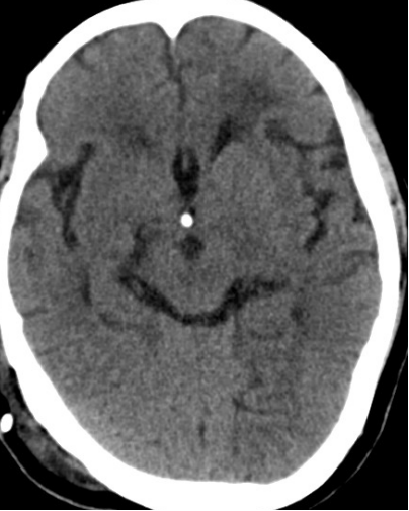

2013-8-2 CT

腰穿脑压240